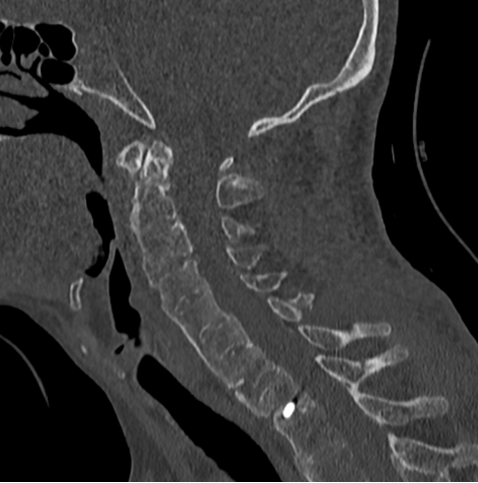

去年,家住昆山的金先生走路的时候不慎摔倒,下颌撞击硬物后感到颈部疼痛难忍,到当地医院查CT显示:(枢椎)齿状突骨折,骨折块向椎管方向移位。齿状突骨折属于上颈椎,位于头颅和颈椎的交界区域,是连接生命中枢的要塞,解剖结构复杂,有椎动脉和中枢神经从中穿过,稍有不慎就会引起大出血、瘫痪、甚至立即死亡。这类手术属于上颈椎手术,曾一度被视为骨科的手术禁区,国内仅有少数医院能够开展这一类手术,一般医师不敢轻易尝试。在业内医师的推荐下,家属送金先生来到了苏州大学附属独墅湖医院,找到了姜为民主任。

接诊后得知,金先生还患有强直性脊柱炎多年,这种疾病直接的后果是脊柱强直如棍棒,骨质变脆易骨折,被冠名以“不死的癌症”。姜主任详细了解金先生的病史后,认为该患者的治疗关键在于以下三个方面:一是脊柱强直,手术部位的位置深难以显露,解剖复杂。二是C2、C3左侧椎弓根发育异常狭小,置入椎弓根螺钉困难。三是齿状突骨折向后方移位明显,通常向前脱位较为常见复位也较容易,此种脱位的复位具有较大的难度和损伤脊髓的风险,对于术者而言是个巨大考验。

金先生伤后第7天,姜主任医师团队在麻醉手术科的密切配合下成功为他实施手术。姜主任凭借多年徒手置钉的过硬技术经验,2小时不到便完成了手术,术中出血仅100ml。术后CT显示齿状突完美复位,螺钉“不偏不倚”的位置恰到好处。术后,金先生在骨科护士长张霞芬护理团队的精心护理下,15天后伤口拆线康复出院。